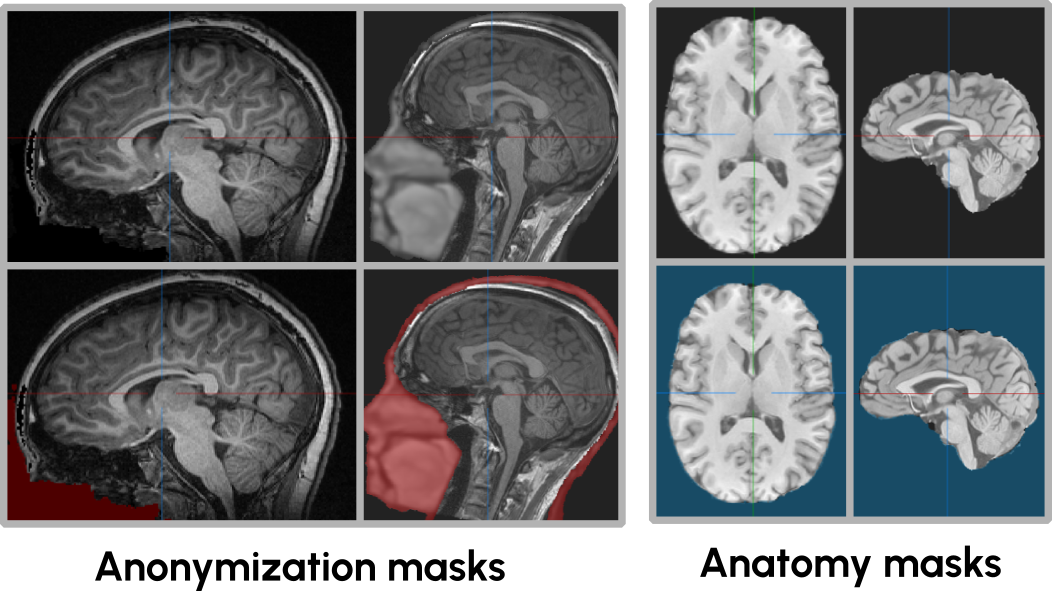

Protecting patient privacy is a big concern in the medical domain, hence, the facial region of Head-and-Neck scans are commonly anonymized. Common anonymization techniques include defacing – replacing the volume with a constant value –, blurring everything but the brain or brain extraction, see Fig. 2. These augmented regions can interfere with reconstruction-based SSL methods, potentially penalizing models for attempting to reconstruct plausible anatomical features in anonymized regions. Therefore, masks delineating these regions are needed to allow excluding them from the loss computation. Unfortunately, not all datasets provide these masks, despite applying some sort of anonymization.

Refer to caption

Figure 2: Head-and-Neck scans are often defaced, have the face blurred or have been brain-extracted to guarantee patient privacy. This can potentially harm reconstruction-based SSL methods. We provide anonymization and anatomy masks to allow taking this into account during method development.

To address this issue, we generate associated anonymization masks and anatomy masks for cases where these are not provided (Fig. 2 bottom). The anonymization mask identifies areas where anatomical structures have been artificially modified or removed and where no loss should be calculated, whereas anatomy masks indicate where relevant foreground is present, allowing to avoid sampling non-empty patches which may speed up the convergence of the pre-training methods. Both of these masks are created using the model proposed by Nohel et al. [31].